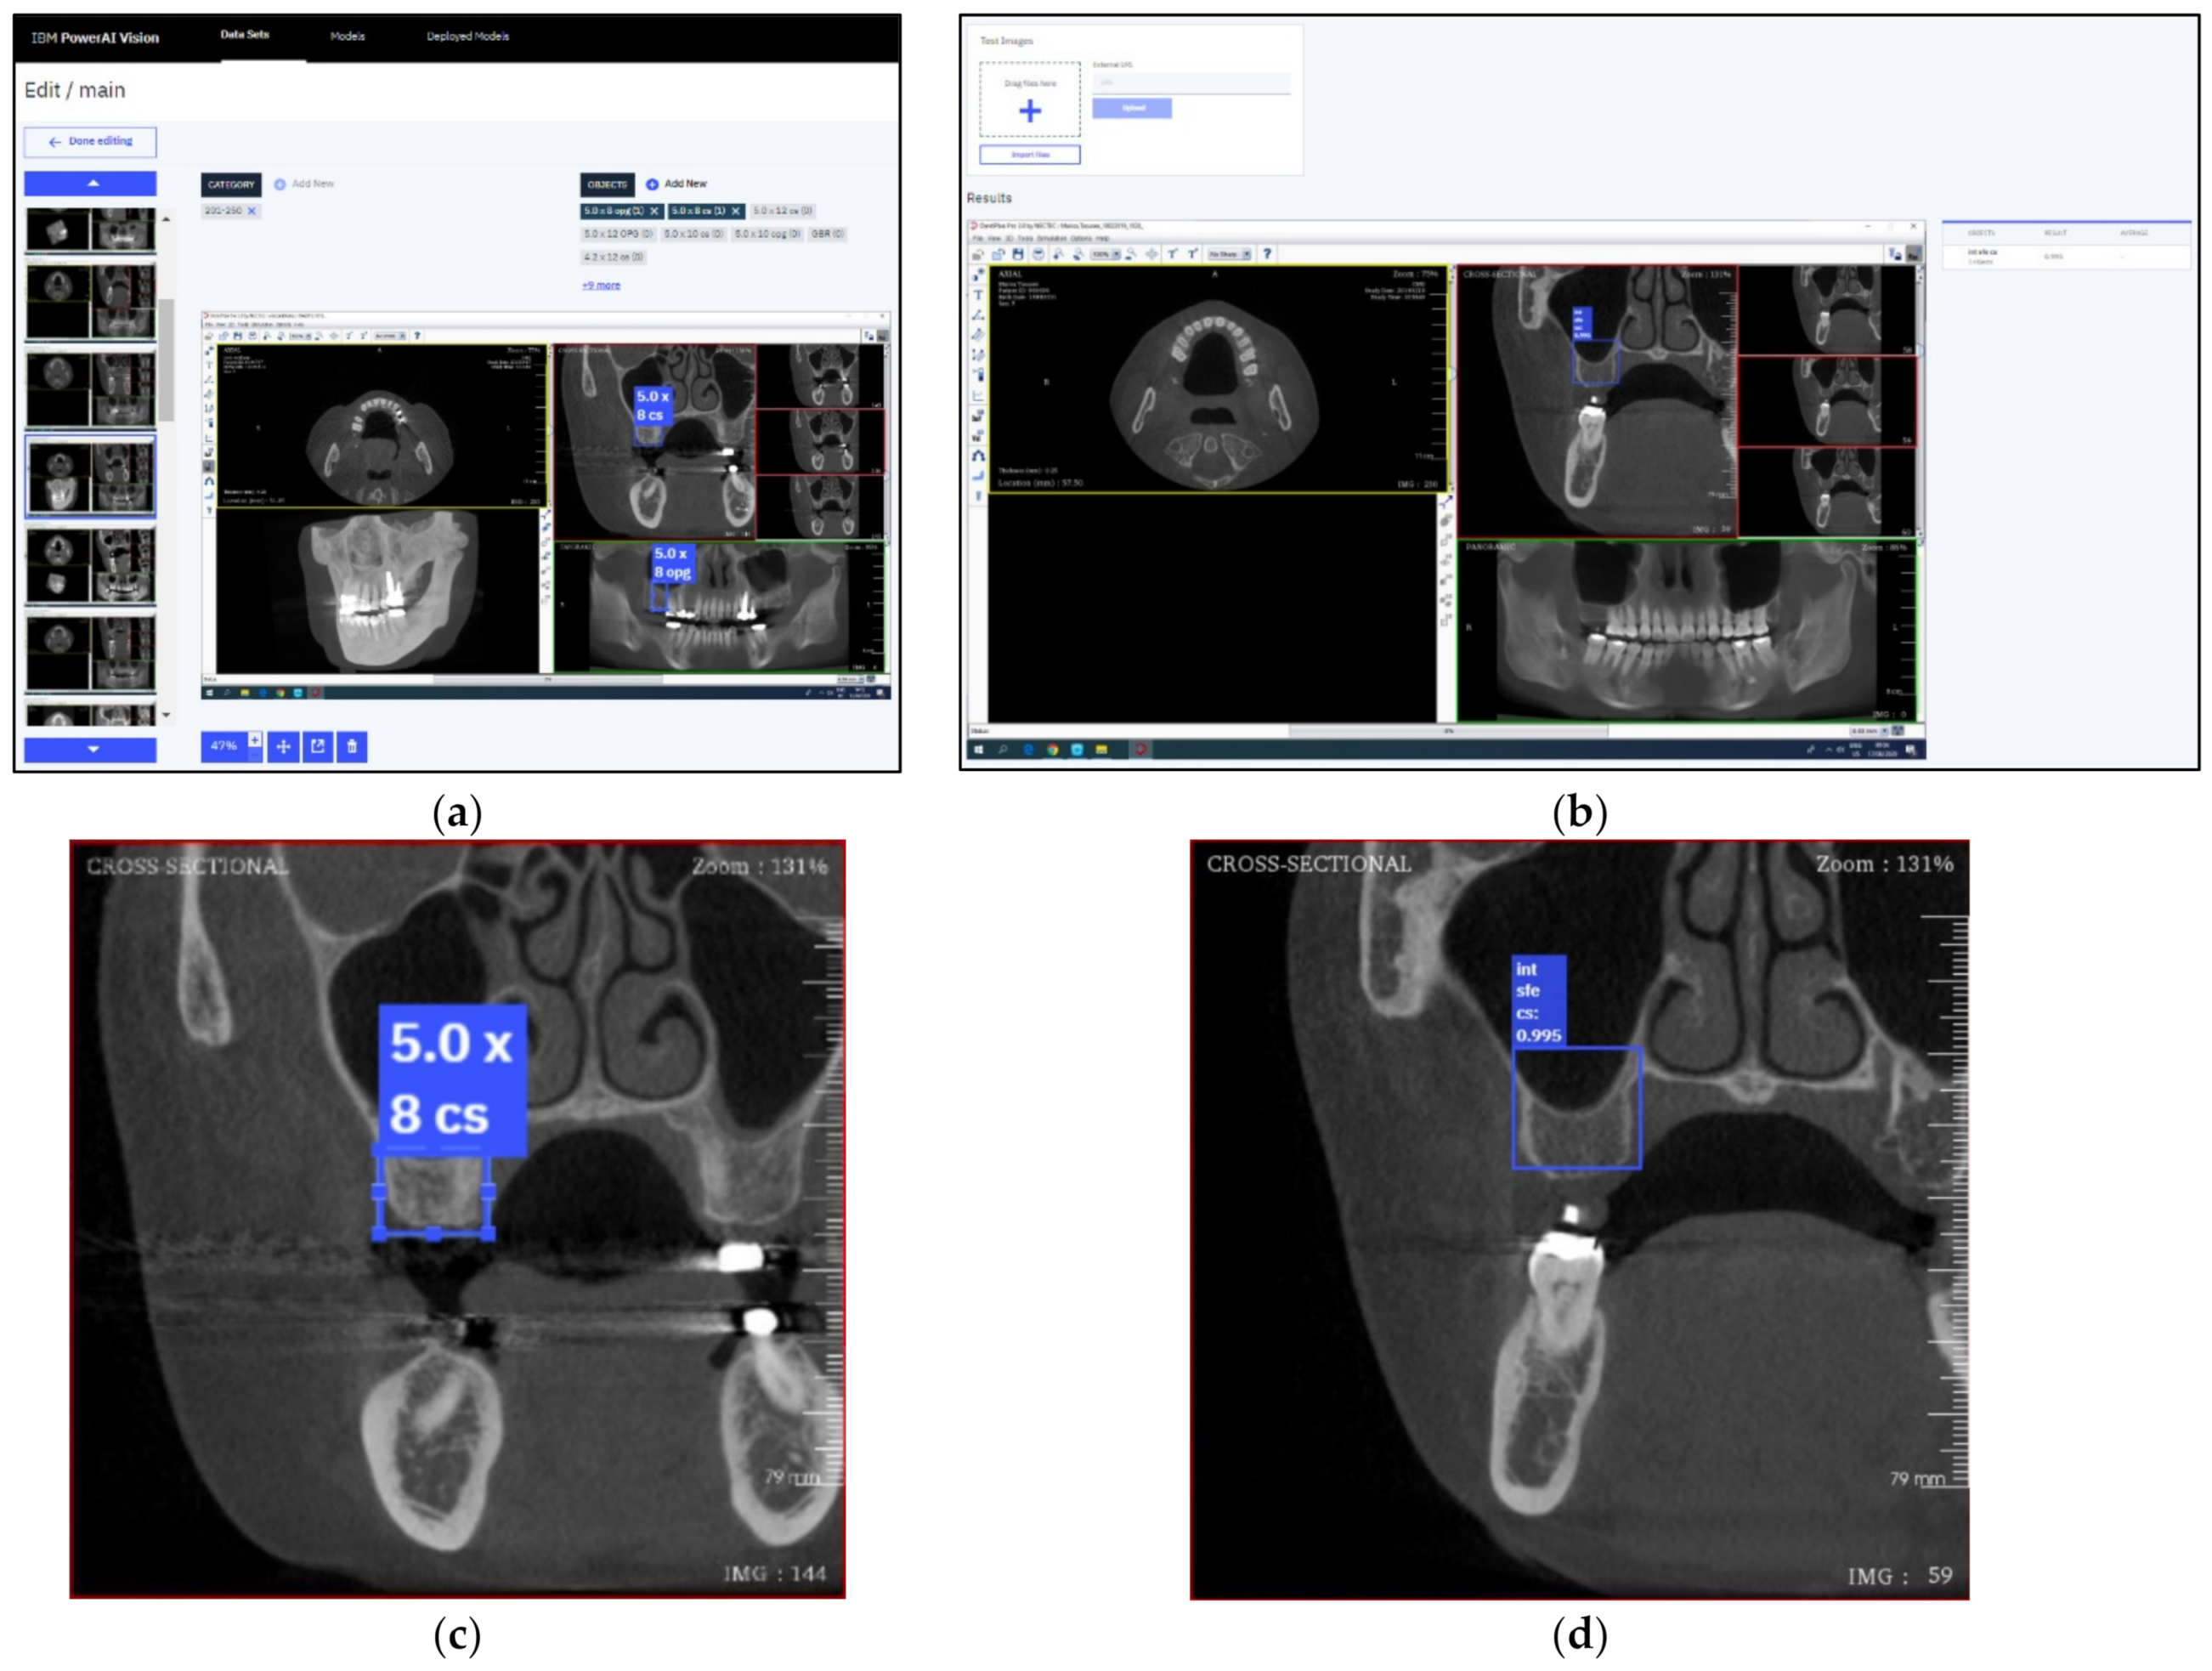

Figure 3.

GUI of the IBM PowerAI Vision platform during the labelling process (a), during the testing process (b), the magnification of cross-sectional image during the labelling process (c), and the magnification of cross-sectional image during the testing process (d).

Subsequently, each labelled area was then annotated with eight different sets, including 4.2 × 8, 4.2 × 10, 4.2 × 12, 5.0 × 8, 5.0 × 10, 5.0 × 12, Int SFE, and Lat SFE for each panoramic and cross-sectional image. The annotations for both panoramic and cross-sectional images were independent because of their own characteristics, and they were indicated with the corresponding labelled box area (as displayed in Figure 3a).

Thereafter, the six original training sets and the new 24 augmented training sets were then utilized to train the AI. The faster R-CNN algorithm was used to develop the AI. The model hyperparameters were configured with the default setting. After 30 training sets were completely trained, the trained model was then deployed and evaluated with the 16 prerequisite images in the testing set which included 2 images of every picture that must be indicated to 4.2 × 8, 4.2 × 10, 4.2 × 12, 5.0 × 8, 5.0 × 10, 5.0 × 12, Int SFE, and Lat SFE. Each testing image was annotated as the ground truth. The testing process required uploading each image one at a time, and the deployed model then displayed the detection with bounding boxes, annotation, and confidence percentage. Each testing image that was uploaded into the deployed model was not included in the development of the model. An example of the testing process is demonstrated in Figure 3b. If the labelled object in the images was indicated with more than an 80% confidence threshold, the annotation results were then recorded throughout the study. The recorded data were analyzed for detection and accuracy. Detection was defined as the event resulting in object detection, and accuracy was defined as the matching outcome between the annotation of the resulting object detection and the actual outcome that was interpreted by the human developer.